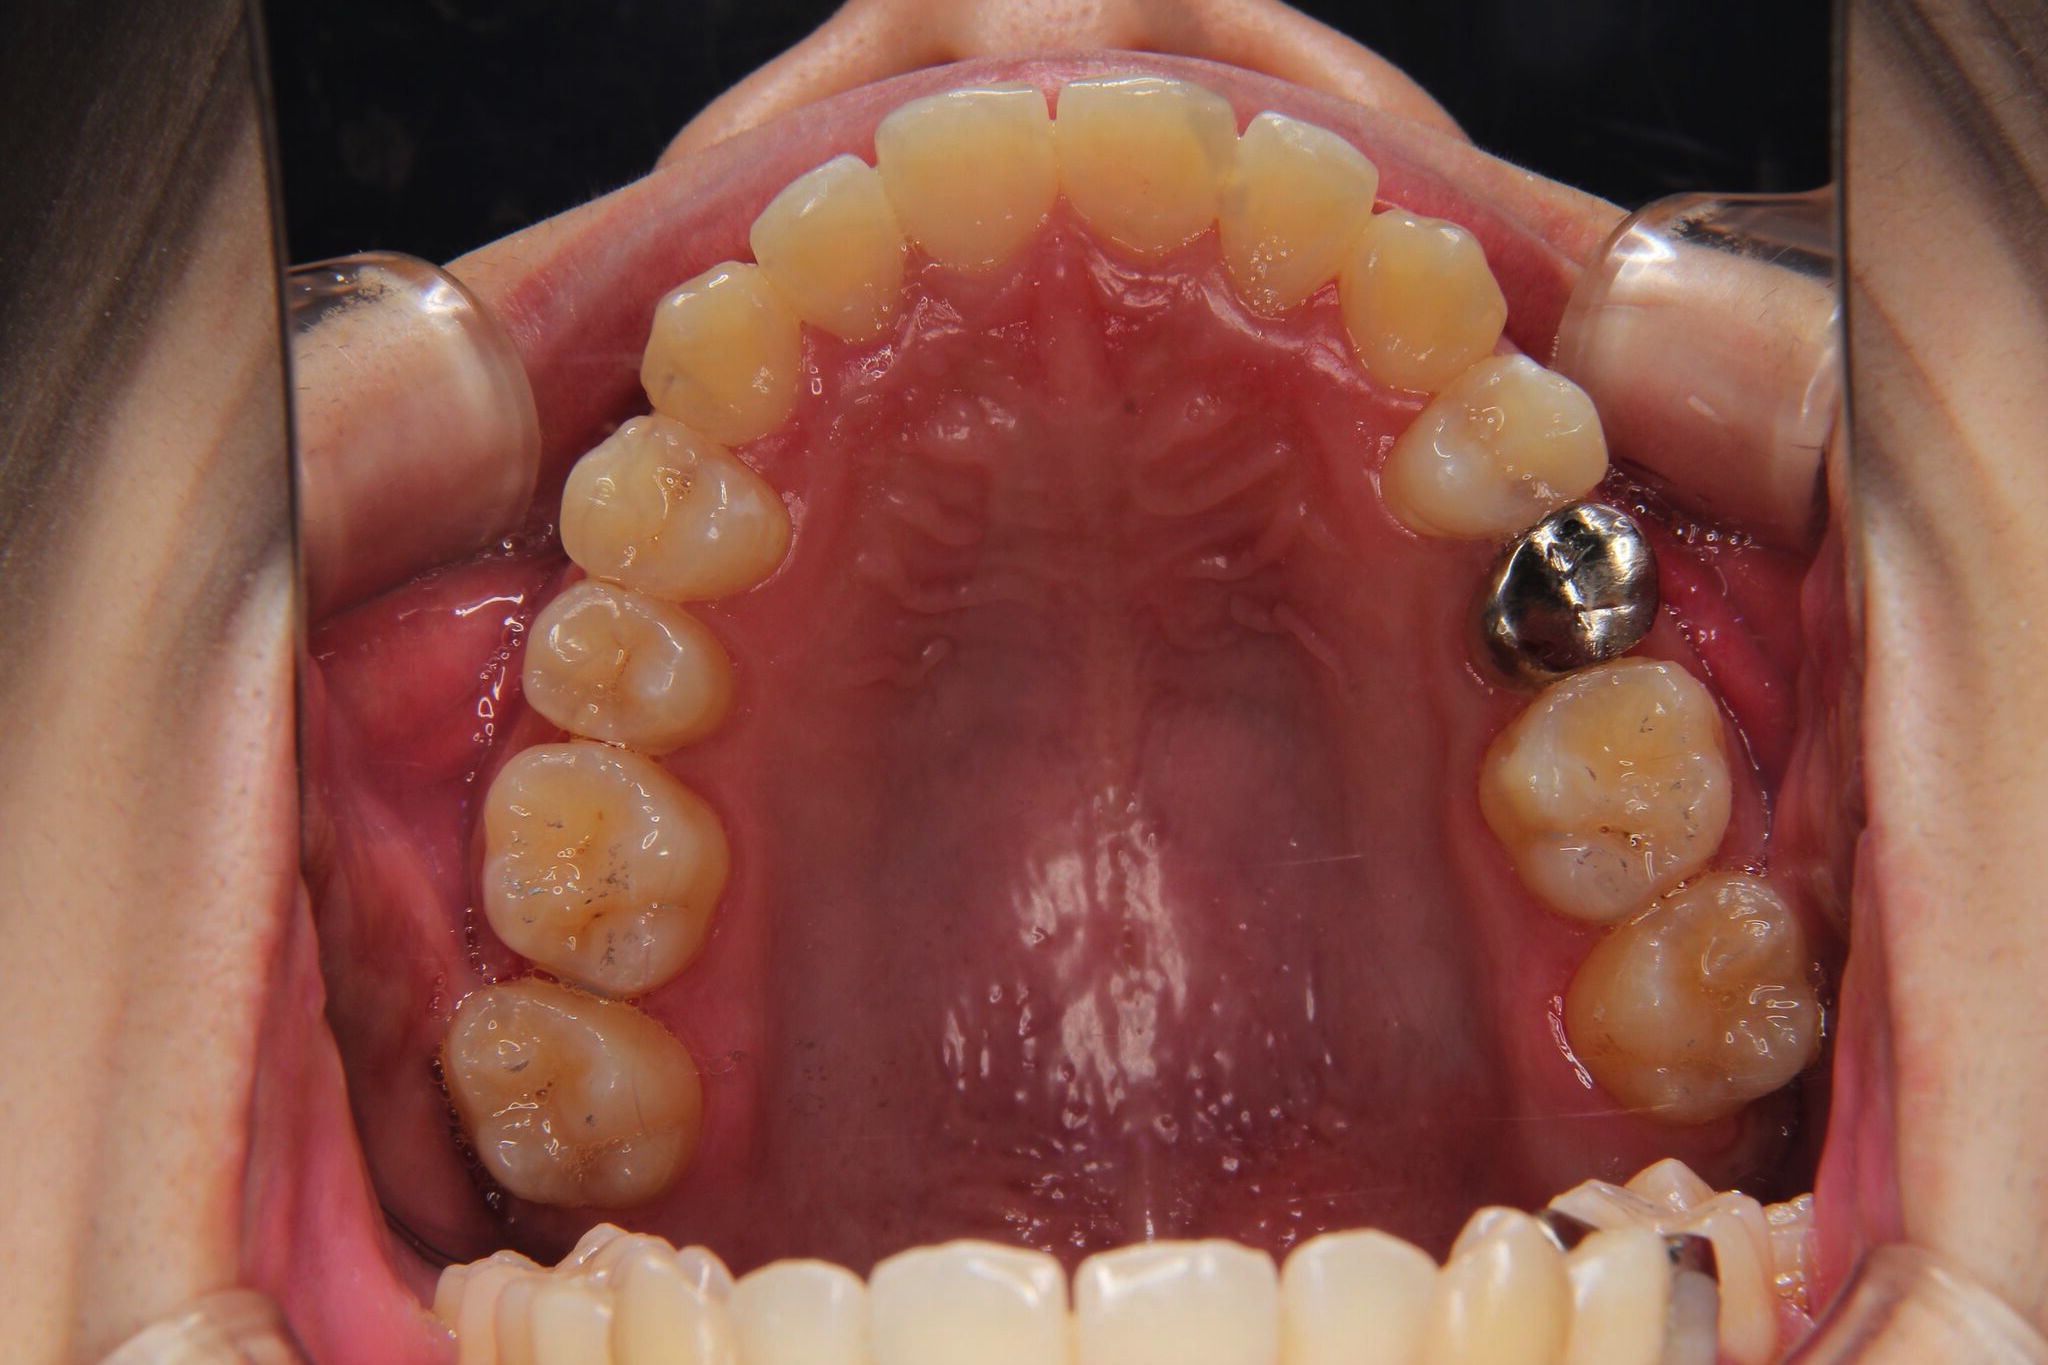

受け口

反対咬合(上顎前歯部叢生)

【患者】 10代 男性

【期間】 1年5カ月

- 治療前 治療後

非抜歯で治療を行いました。

- 上顎大臼歯部の遠心移動

- 下顎歯列全体のアップライティング